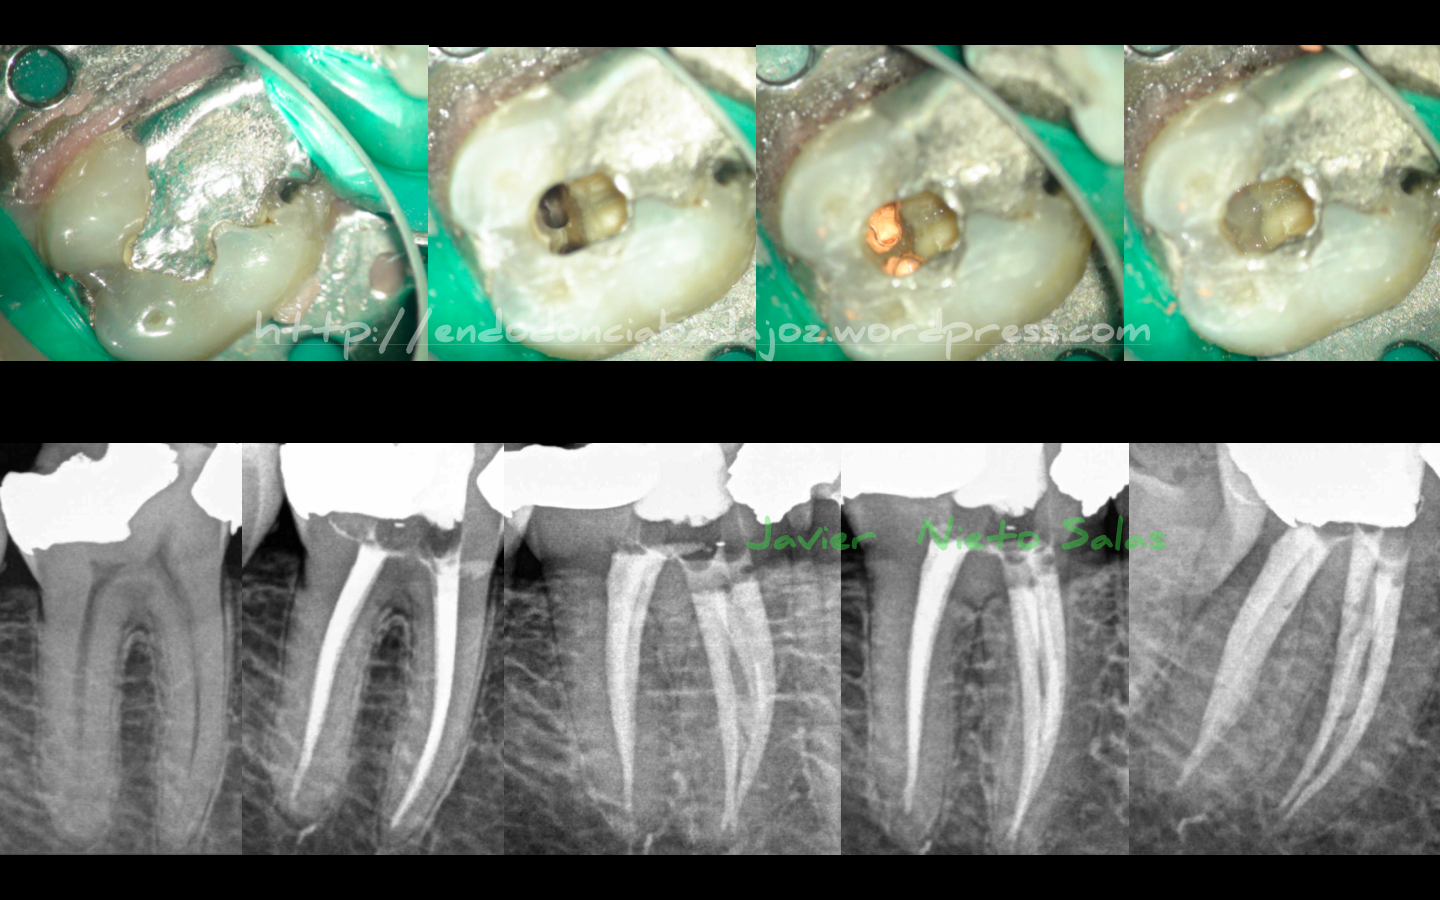

Hoy en día se está hablando demasiado de las «Aperturas Ninja», creo que es un concepto equivocado, se trata de llamarlo «apertura conservadora» que consiste en estudiar el caso y ver la cantidad SUFICIENTE y MÍNIMA para realizar un correcto tratamiento de conductos. Entre las ventajas, se encuentra conservar mayor estructura dentinaria que es tan importante para supervivencia del diente en el tiempo. Y como desventaja principal, que se complica el tratamiento mucho, en cuanto a desinfección , conformación y obturación de conductos.

Sigo apostando por esta «apertura conservadora»:

La anatomía de los molares inferiores es bastante aberrante, sus anastomosis entre conductos, bifurcaciones y demás hacen de esta pieza una de las más complicadas de tratar. Estas que colocamos no son casos complicados, pero de igual forma hemos intentado manejarlos correctamente.

Por contra, los molares superiores, que para mí son los más complicados de tratar, presentan, más que 3, 4 o más conductos, presentan istmos o plexos de sistema de conductos, que los trataremos como conductos, haciendo de estos, casos más o menos bonitos, pero con un trabajo muy intenso. Aquí os dejo un caso de como tratamos el istmo del conducto MV.

Este caso tiene la particularidad de tener 5 conductos, 3 mesiales y dos distales. Se trata de un 4.7 con una necrosis pulpar con periodontitis apical asintomática. Se instrumentó con Reciproc y Mtwo. El conducto Distal se talló también con ultrasonidos. La técnica de obturación fue con Condensación Vertical con Ola continua de calor modificada y un backfilling con sistema de gutapercha inyectada de B&L.